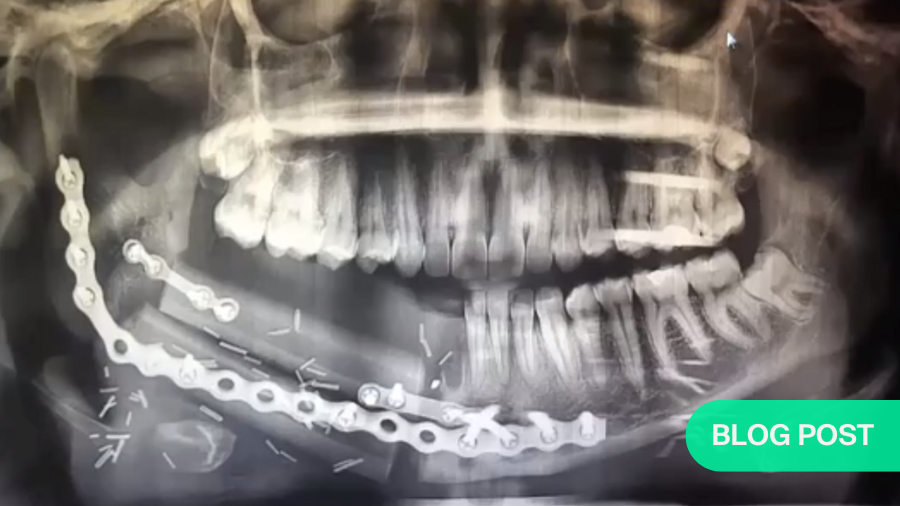

For example, free flaps are normally indicated for circumferential pharyngoesophageal reconstruction, class III or higher defects of the maxilla, and composite defects in mandibular reconstruction. When used for salvage total laryngectomy, they reduce the incidence of pharyngocutaneous fistulae.

Particularly where a flap is used to increase bulk, some degree of retraction normally occurs. This process can continue for a very long time. Therefore, in cases where a massive resection of the tongue and mandibulotomy have been necessary, a slightly-oversized ALT flap (with bone taken from the femur, if necessary ) will allow for shrinkage over a period of ten or more years.

Naturally, there are exceptions. For example, if we need to increase the height of mandible via distraction, but the patient is scheduled for radiation treatment, it is advisable to wait three to six months after the radiotherapy before beginning the distraction process. And the process itself will require daily adjustments.